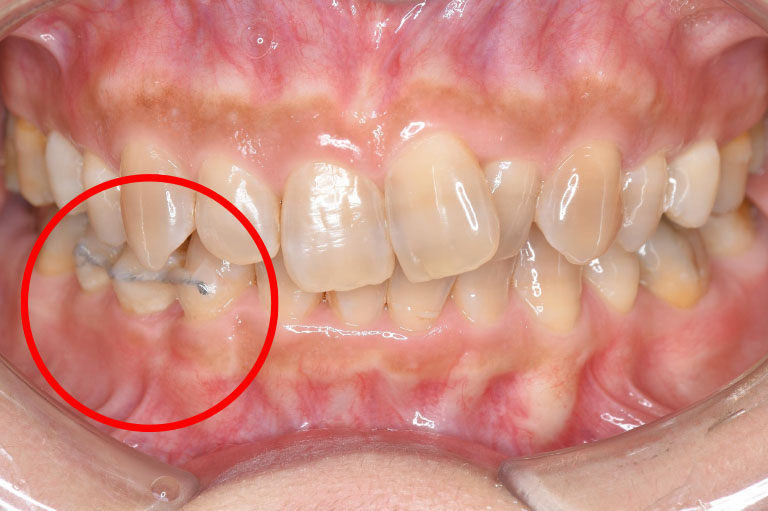

case.1

治療後

| 治療名 | 歯周組織再生療法 |

| 患者様情報 | 50代 女性 |

| 担当医 | 亀岡 聡貴 先生 |

| 費用 | 15.000円 (税込) 保険内 |

| 主訴 | 右下3番付近の歯茎が 1週間前から腫れている。 |

| 治療期間 | 1年 |

| 治療内容 | 歯周基本治療(SRP、TBI、咬合調整など)+歯周外科治療(再生療法)を行いました。全顎的に歯茎の炎症も落ち着き、レントゲン上でも骨の再生を認められました。 |

| 治療のリスク | 現在の状態の維持のため、継続的にメインテナンスを行う必要があります。 |